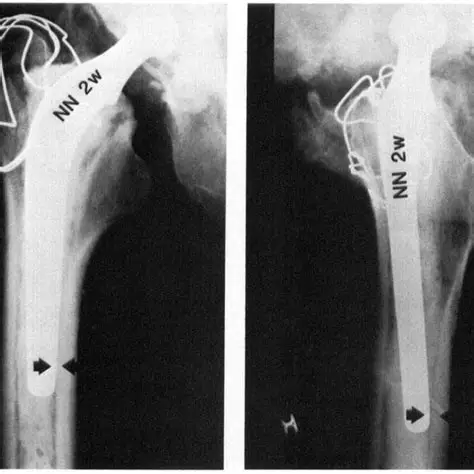

1. Spinal Tuberculosis (Pott’s Disease) Explained By Dr. Jitesh Manghwani

Spinal TB remains a common yet challenging condition in orthopedic practice. In this highly viewed session, Dr. Jitesh Manghwani simplifies a complex topic with excellent clinical clarity.

• Pathophysiology of spinal TB

• Key clinical features and red flags

• X-ray and MRI findings

• Complications like kyphosis and neurological deficits

• Principles of medical and surgical management

A must-watch for residents, students, and exam aspirants alike.